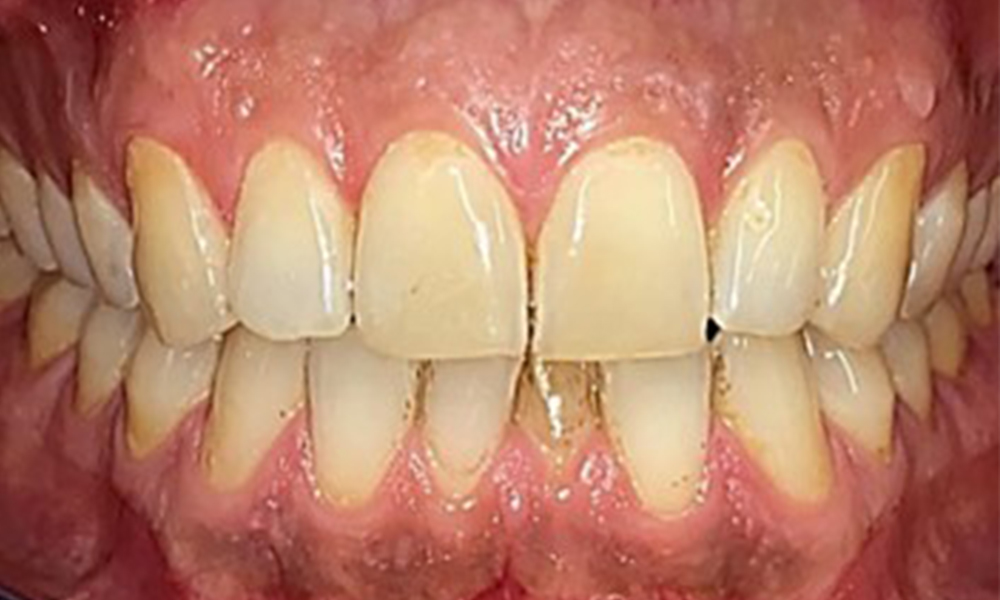

There were no pathological extraoral findings. During intraoral examination, inspection of the frontal view revealed brownish discolouration near the keratinised gingiva and at the transition to the moveable mucosa (Fig. 2), which could be attributed to nicotine consumption. Whitish mucosal lesions were observed on the palate, particularly near the maxillary molar palatal surfaces, indicating increased keratinisation and can also be attributed to nicotine consumption. The tongue was covered with a removable white and brownish coating.

The patient has full dentition with a total of 28 teeth. There were noteworthy erosions and attritions. (Fig. 4, Fig. 5). Due to bruxism, the patient has been wearing a splint with an adjusted bite block at night for many years. The erosions were caused by long-term consumption of isotonic beverages. No periodontal bone loss or active caries were observed.